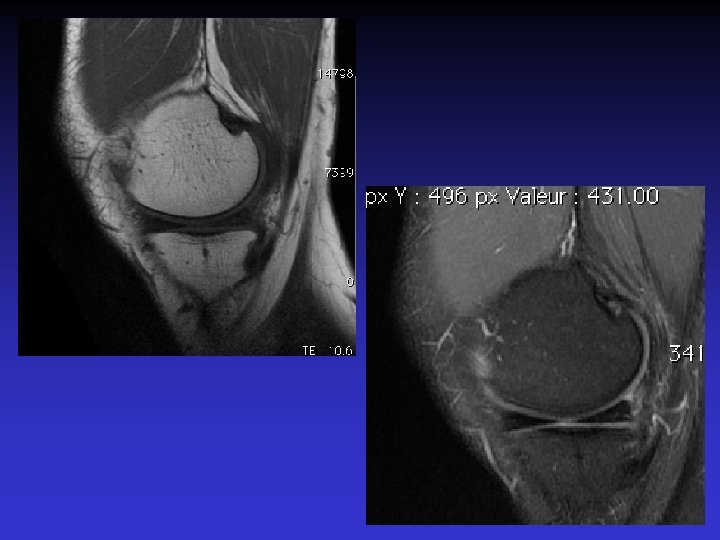

ASPECT IRM • • Hyposignal TI Hypersignal T 2 Pas de prise du contraste après Gado IV Continuité conservée du LCA+++ avec dilacération des fibres • Aspect en « tige de céleri »

GADO

GEODES SYNOVIALES • En regard des zones d’insertion fémorale et / ou tibiale • Hypo TI Hyper T 2 • Rehaussement possible après Gado IV